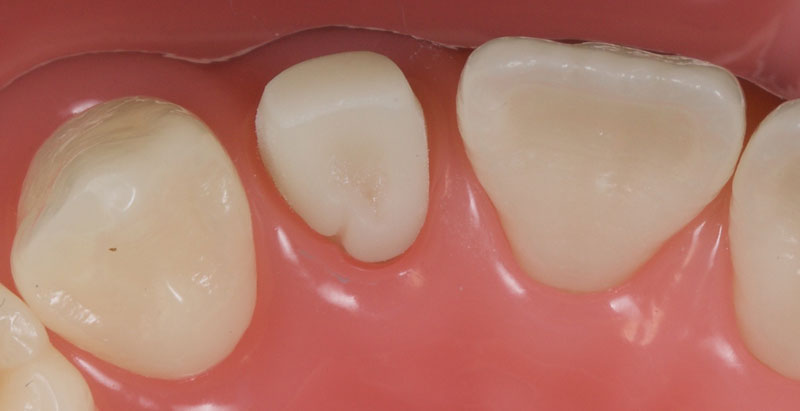

- Single Tooth: This is a microdontia localized to one tooth. Most peg laterals seen in a general dental practice setting will be of this type. See Fig. 3 (pre-op) and Fig. 4 (immediate post-op treated with direct resin).

- Treatment planning: The assessment can be done simply via clinical examination, though study casts/scans may be employed if they are available. The peg lateral should be observed from the occlusal aspect (Fig. 5).

Ideally, the tooth should be in the center of the space mesio-distally, so the mesial and distal gingival emergence profiles are optimized. Furthermore, the incisal-facial portion of the tooth must be around 1 mm palatal to the adjacent canine and central incisor — that is, the peg lateral needs to be slightly palatally placed.

In my experience, the most common reason for the peg lateral restoration’s restorative failure is inadequate restorative space, which results in a bulky buccally placed veneer.